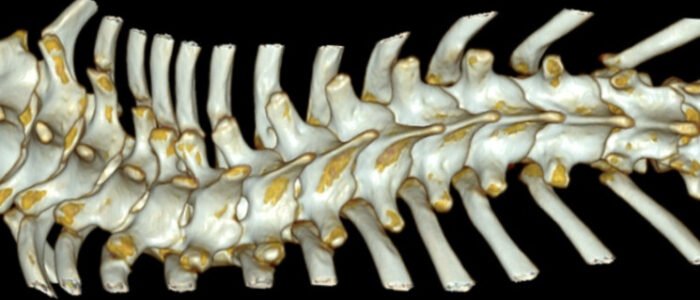

Children’s spines undergo rapid growing and are more flexible,and neurologically distinct.

They’re prone to conditions like scoliosis, kyphosis, and spondylolisthesis.

Early detection and growth-sensitive care are essential to prevent long-term deformity and support healthy spinal development.

Adolescent spines undergo rapid growth and hormonal changes, making them prone to scoliosis, hyperkyphosis, and back pain.

Monitoring during puberty is vital, as spinal curves can progress quickly and impact posture, function, and long-term musculoskeletal health.

The adult spines, fully matured, supports mobility and daily function.

Trauma, degeneration, inflammation, and repetitive strain can disrupt biomechanics, causing pain and reduced flexibility.

Proactive care helps preserve spinal health and sustain quality of life.

The aging spines undergo disc dehydration, bone loss, and joint degeneration.

These changes increase the risk of joint pain, fractures, and deformity.

Managing osteoporosis, mobility, and comorbidities is key to preserving function and quality of life in older adults.